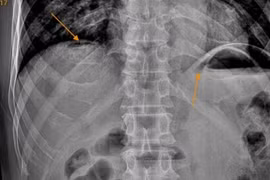

Người đàn ông đến bệnh viện khám trong tình trạng đau bụng đột ngột dữ dội như dao đâm vùng thượng vị, sau đau lan khắp ổ bụng,... Bệnh nhân được chẩn đoán viêm phúc mạc do thủng tạng rỗng.